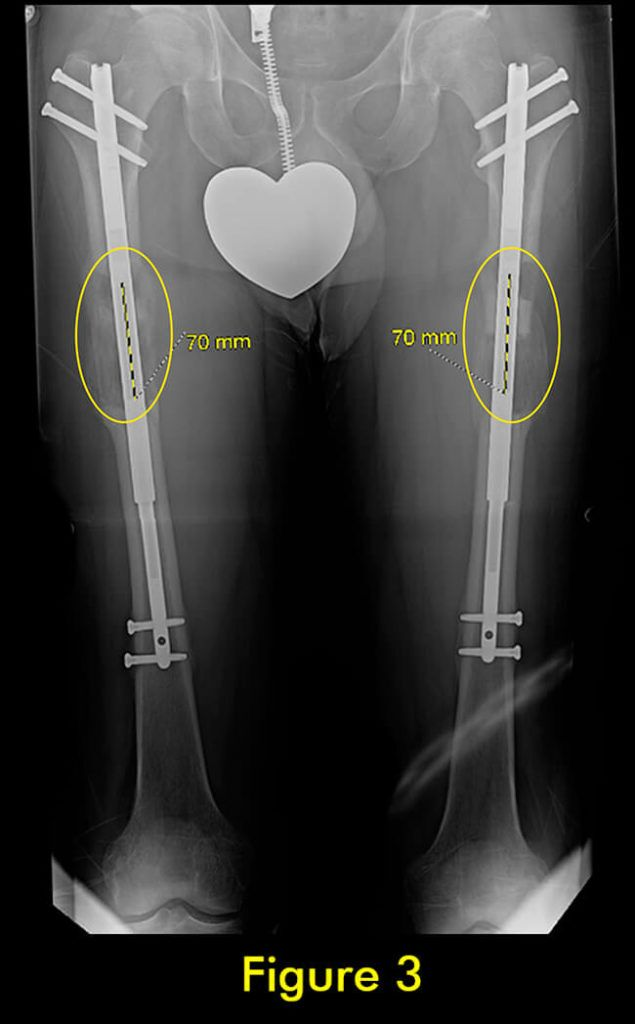

7 腓骨并发症

随着胫骨的延长,腓骨也必须延长。植入式加长装置仅延长和固定胫骨。腓骨必须固定在胫骨上,以便它与胫骨一起拉长。如果腓骨固定不固定或固定不充分,它不会像胫骨那样拉长,并会导致严重的后果,包括脚踝半脱位和关节炎以及膝盖屈曲挛缩。

固定方法至关重要。许多外科医生只将腓骨的下端固定在胫骨上。这会导致腓骨过早巩固,并在其上端从胫骨向下拉和脱臼。固定腓骨两端很重要。大多数外科医生避免这样做,因为这在技术上很难做到。

我们为所有患者的腓骨两端固定。植入式加长时,腓骨必须用螺钉固定在胫骨上;上端有一个螺钉,下端有一个螺钉。螺钉的角度、水平、位置、直径和类型都很重要。一个常见的错误是将螺钉水平放入两块骨头之间。这不足以防止腓骨从脚踝处的胫骨上拉开。这是非常微妙的,即使脚踝腓骨长度的几毫米差异也会给患者带来短期和/或长期后果。切除腓骨的一部分以防止腓骨不分离是另一种应避免的常见方法。它会导致腓骨不愈合,从而导致胫骨以后出现应力性骨折。

此外,它通常不会阻止腓骨从胫骨上拉开。因此,腓骨并发症与植入式延长装置的类型无关,而是与外科医生选择将腓骨固定到胫骨的方法和切割腓骨的方法有关。腓骨愈合的范围可以从过早巩固到完全不愈合。后者通常不需要治疗,只要胫骨牢固愈合。前者需要重复腓骨截骨术。

在外部机构胫骨身材延长并出现双侧并发症的患者。他发展了胫骨和 Abu/a 延迟结合,右侧是敲击 {外翻),左侧是弓形 {内翻),两侧是 f1exion {procurvatum}。我们在手术室使用临时外部斧头机对两侧进行了急性矫正,并放置了新的胫骨杆。我们在 Abu/a 延迟结合上放置了逆行杆。